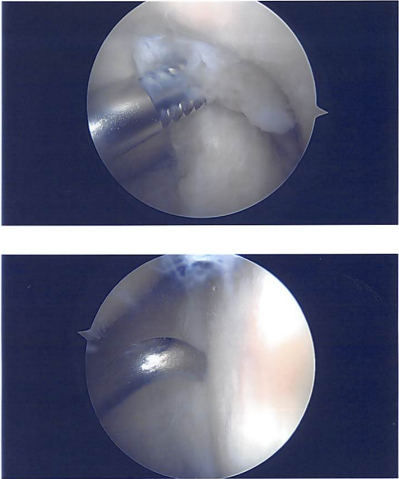

Examination of the lateral tibiofemoral compartment showed bucket handle tear of the lateral meniscus, which was rotated into the intercondylar notch. The meniscus was not able to be reduced easily and was stretched. The meniscus was released anteriorly and posteriorly at the good level. The meniscus was reduced with difficulty.

Speculum was inserted to avoid injury to the posterior and medial aspects of the neurovascular bundles. Repair of the lateral meniscus was done with the use of inside out sutures using zone specific cannulas x3, use of Final pictures were taken and saved.

Intraoperative images